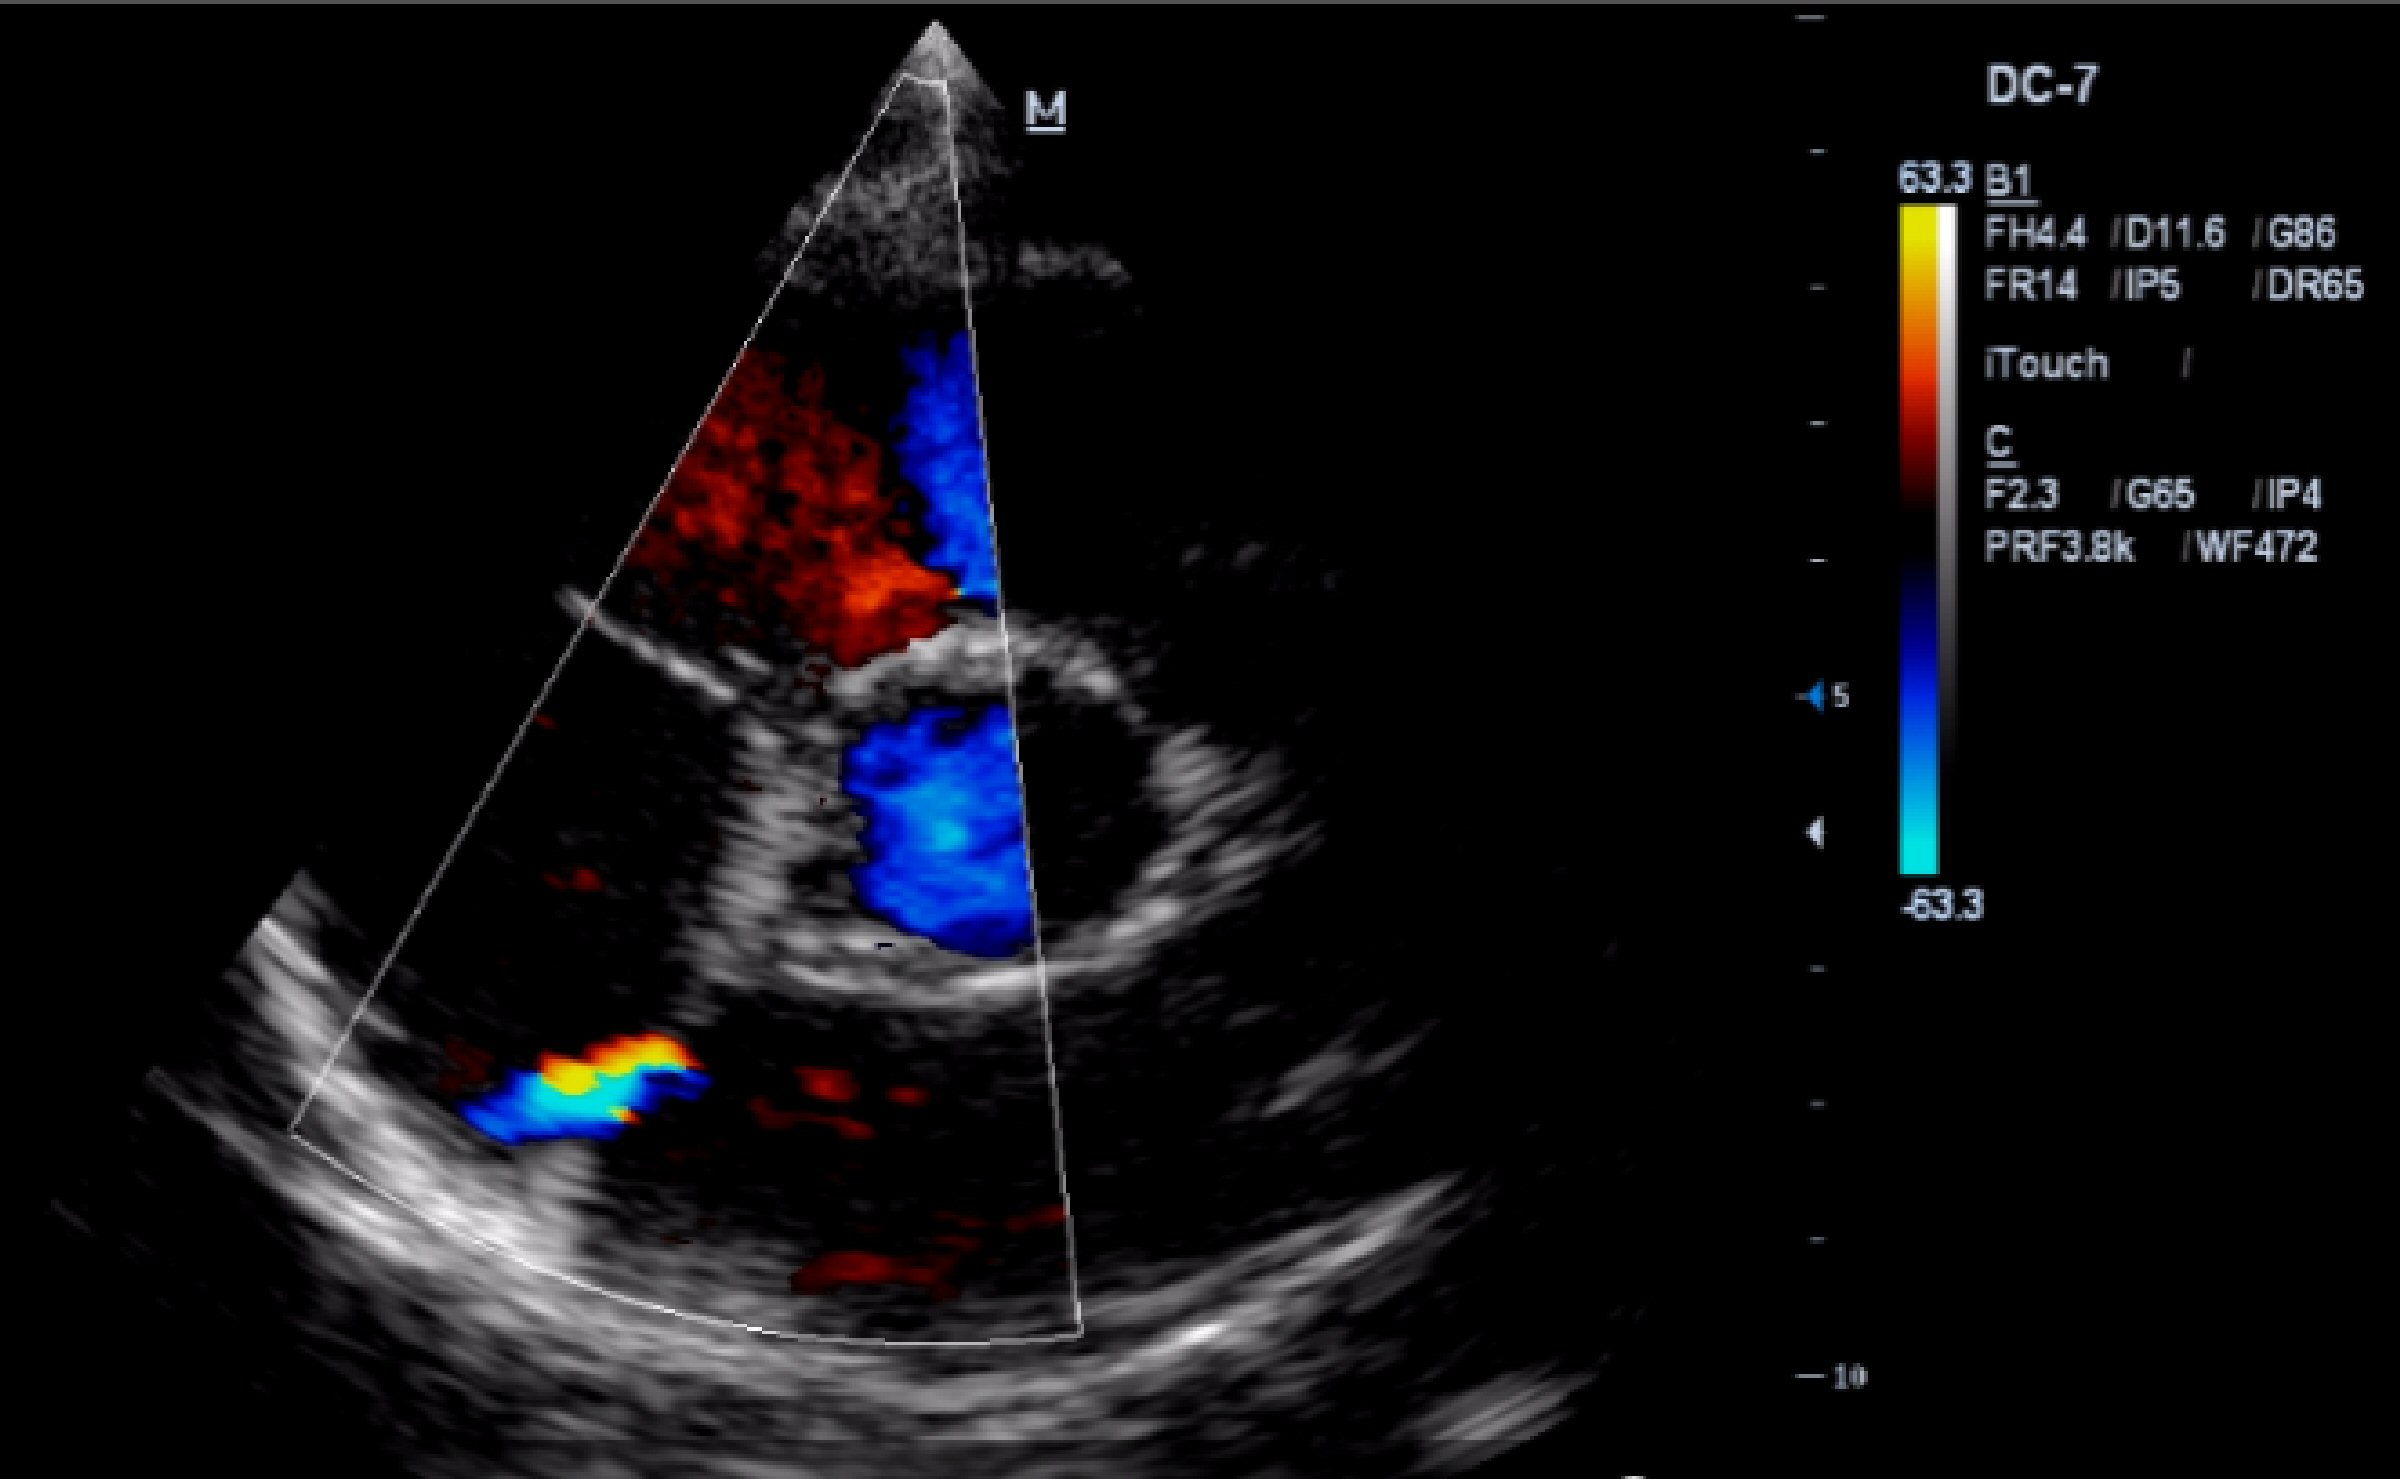

The transthoracic echocardiogram (TTE) shows a mildly dilated LV (adjusted for body surface area, 3.2 cm/m2), but with the rest of cardiac chambers within normal limits, a thickened MV, mainly the anterior MV, with an adjacent calcified cord. The MV closes with grade 2 - 3 mitral regurgitation with eccentric jet pointing to the posterior wall of the left atrium, but without the appearance of MV prolapse. The aortic valve appears tricuspid, thickened. An ostium secundum ASD is noted, with left to right shunt (Fig. 3). The TTE also reveals trabeculations of the LV lateral wall (Fig. 4), septal and anterior wall hypokinesis, and global LV ejection fraction of 50%.

![]() Click for large image | Figure 3. TTE (parasternal short axis view): ASD with left to right shunt. |